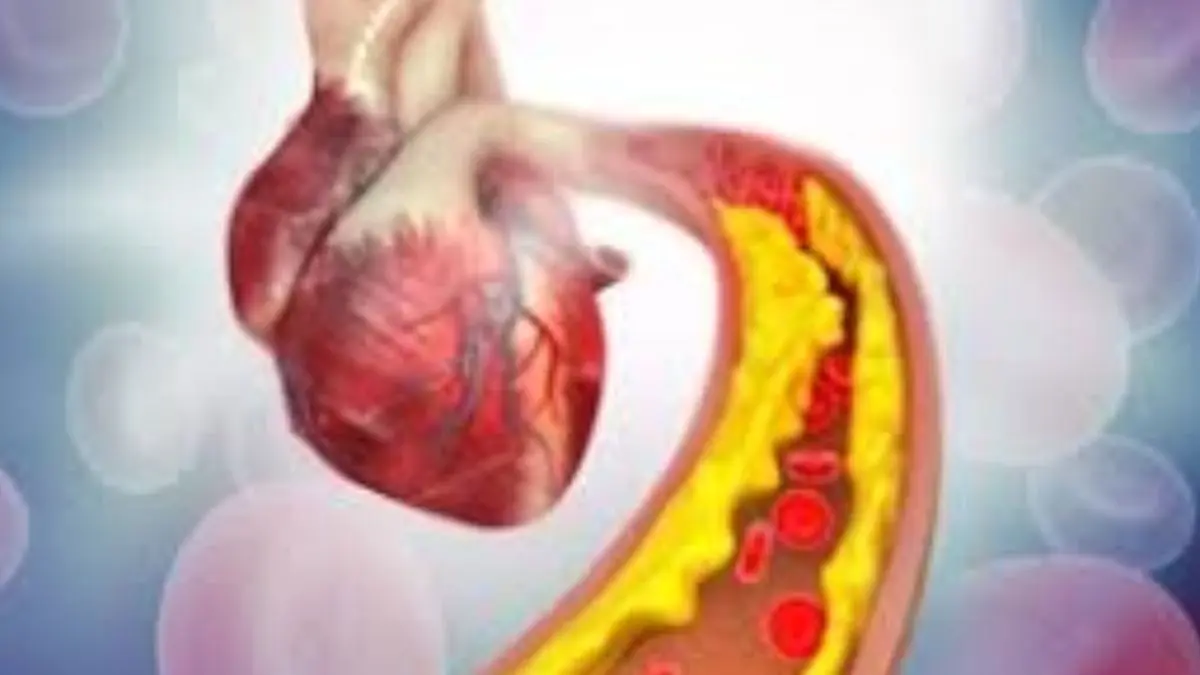

Cholesterol Control Tips: આપણે કોલેસ્ટ્રોલને આપણા સ્વાસ્થ્ય માટે ખતરો માનીએ છીએ અને તે યોગ્ય પણ છે. કોલેસ્ટ્રોલનું લેવલ વધવાથી હૃદય રોગનું જોખમ વધી શકે છે . જોકે ગુડ કોલેસ્ટ્રોલ આપણા શરીર માટે જરૂરી છે. તે હોર્મોન બનાવવા, સેલ બિલ્ડિંગ અને વધુમાં મહત્વપૂર્ણ ભૂમિકા ભજવે છે.

- બધા પ્રકારના કોલેસ્ટ્રોલ ખરાબ છે. ઘણા લોકો માને છે કે કોલેસ્ટ્રોલ ફક્ત શરીર માટે હાનિકારક છે જ્યારે આ અડધું સાચું છે. હકીકતમાં, ગુડ કોલેસ્ટ્રોલ ધમનીઓમાંથી ખરાબ કોલેસ્ટ્રોલને દૂર કરે છે અને જ્યારે તે હૃદયનું રક્ષણ કરે છે, ત્યારે ખરાબ કોલેસ્ટ્રોલ ધમનીઓમાં એકઠું થાય છે અને અવરોધનું કારણ બને છે.

કોલેસ્ટ્રોલ વિશેની આ ગેરમાન્યતાઓ કાં તો લોકોને વધુ પડતી ડરાવે છે અથવા તેમને બેદરકાર બનાવે છે. સત્ય એ છે કે તે શરીરનો એક આવશ્યક ઘટક છે જેને સંતુલિત જીવનશૈલી, નિયમિત તપાસ અને તબીબી સલાહ દ્વારા સરળતાથી નિયંત્રિત કરી શકાય છે. તેથી, મિથક પર નહીં હકીકતો પર વિશ્વાસ કરો અને સ્વસ્થ હૃદય જાળવી રાખો.